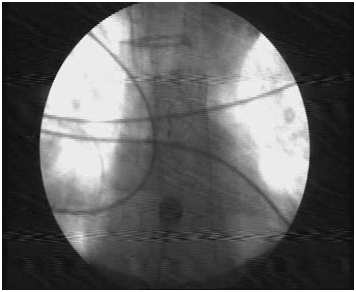

Antimicrobials were escalated empirically. Upper GI endoscopy revealed diffuse mucosal oozing from the lower end of esophagus along with small isolated gastric varix. Glue injection was done, however patient continued to bleed despite supportive measures. Repeat UGI scopy was done, which showed continued generalized ooze from lower end of esophagus. Therefore endoscopic guided Ella danis SEMS was placed with upper end at 25 cm from GE junction. The patient was stabilized and moved to the intensive care unit. There was no subsequent evidence of upper GI bleed. Patient however continued to deteriorate due to pulmonary sepsis. He later succumbed and expired on POD 22 (Figure 1) (Figure 2).

Figure 2 X ray view of Dannis Ella stent in situ.